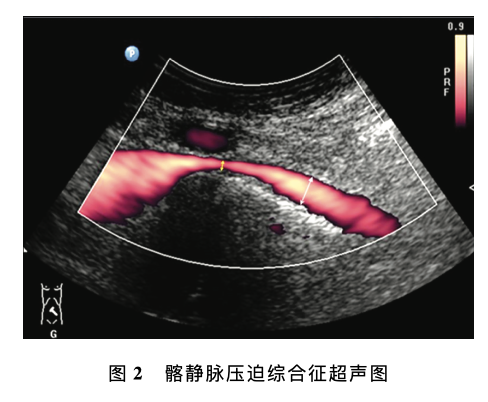

腹部及外周静脉血管超声若干临床常见问题专家共识

意见一:下肢静脉反流超声检查的推荐体位推荐体位为头高脚低位 (建议使用电动检查床), 即检查床头侧高于足侧,与地面夹角约30。条件有限的情况下可选择站立位或坐位,不推荐俯卧位评价下肢静脉反流。意见二:Valsalva (乏氏动作)的适用性乏氏动作主要用于评估隐-股静脉瓣、股静脉近 端静脉瓣的功能,不适于下肢远端静脉反流......